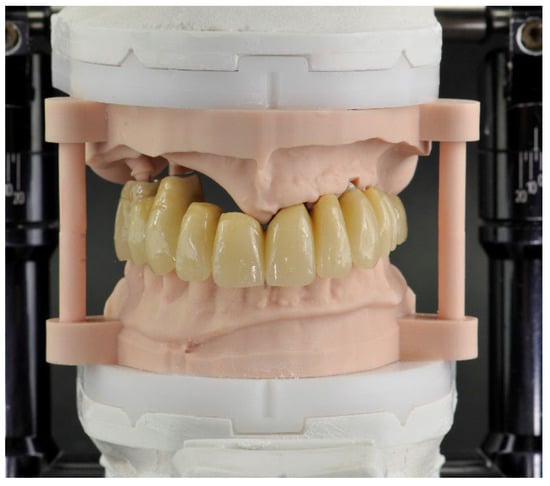

The details of this procedure were reported in previous publications by the same team of authors of this work [,]. The 3D printed model used in this work allowed checking of the final occlusion, and finishing/polishing the provisional prosthesis (Figure 9).

Figure 9.

Immediate provisional prosthesis in Titanium and PMMA articulated with the inferior arch.